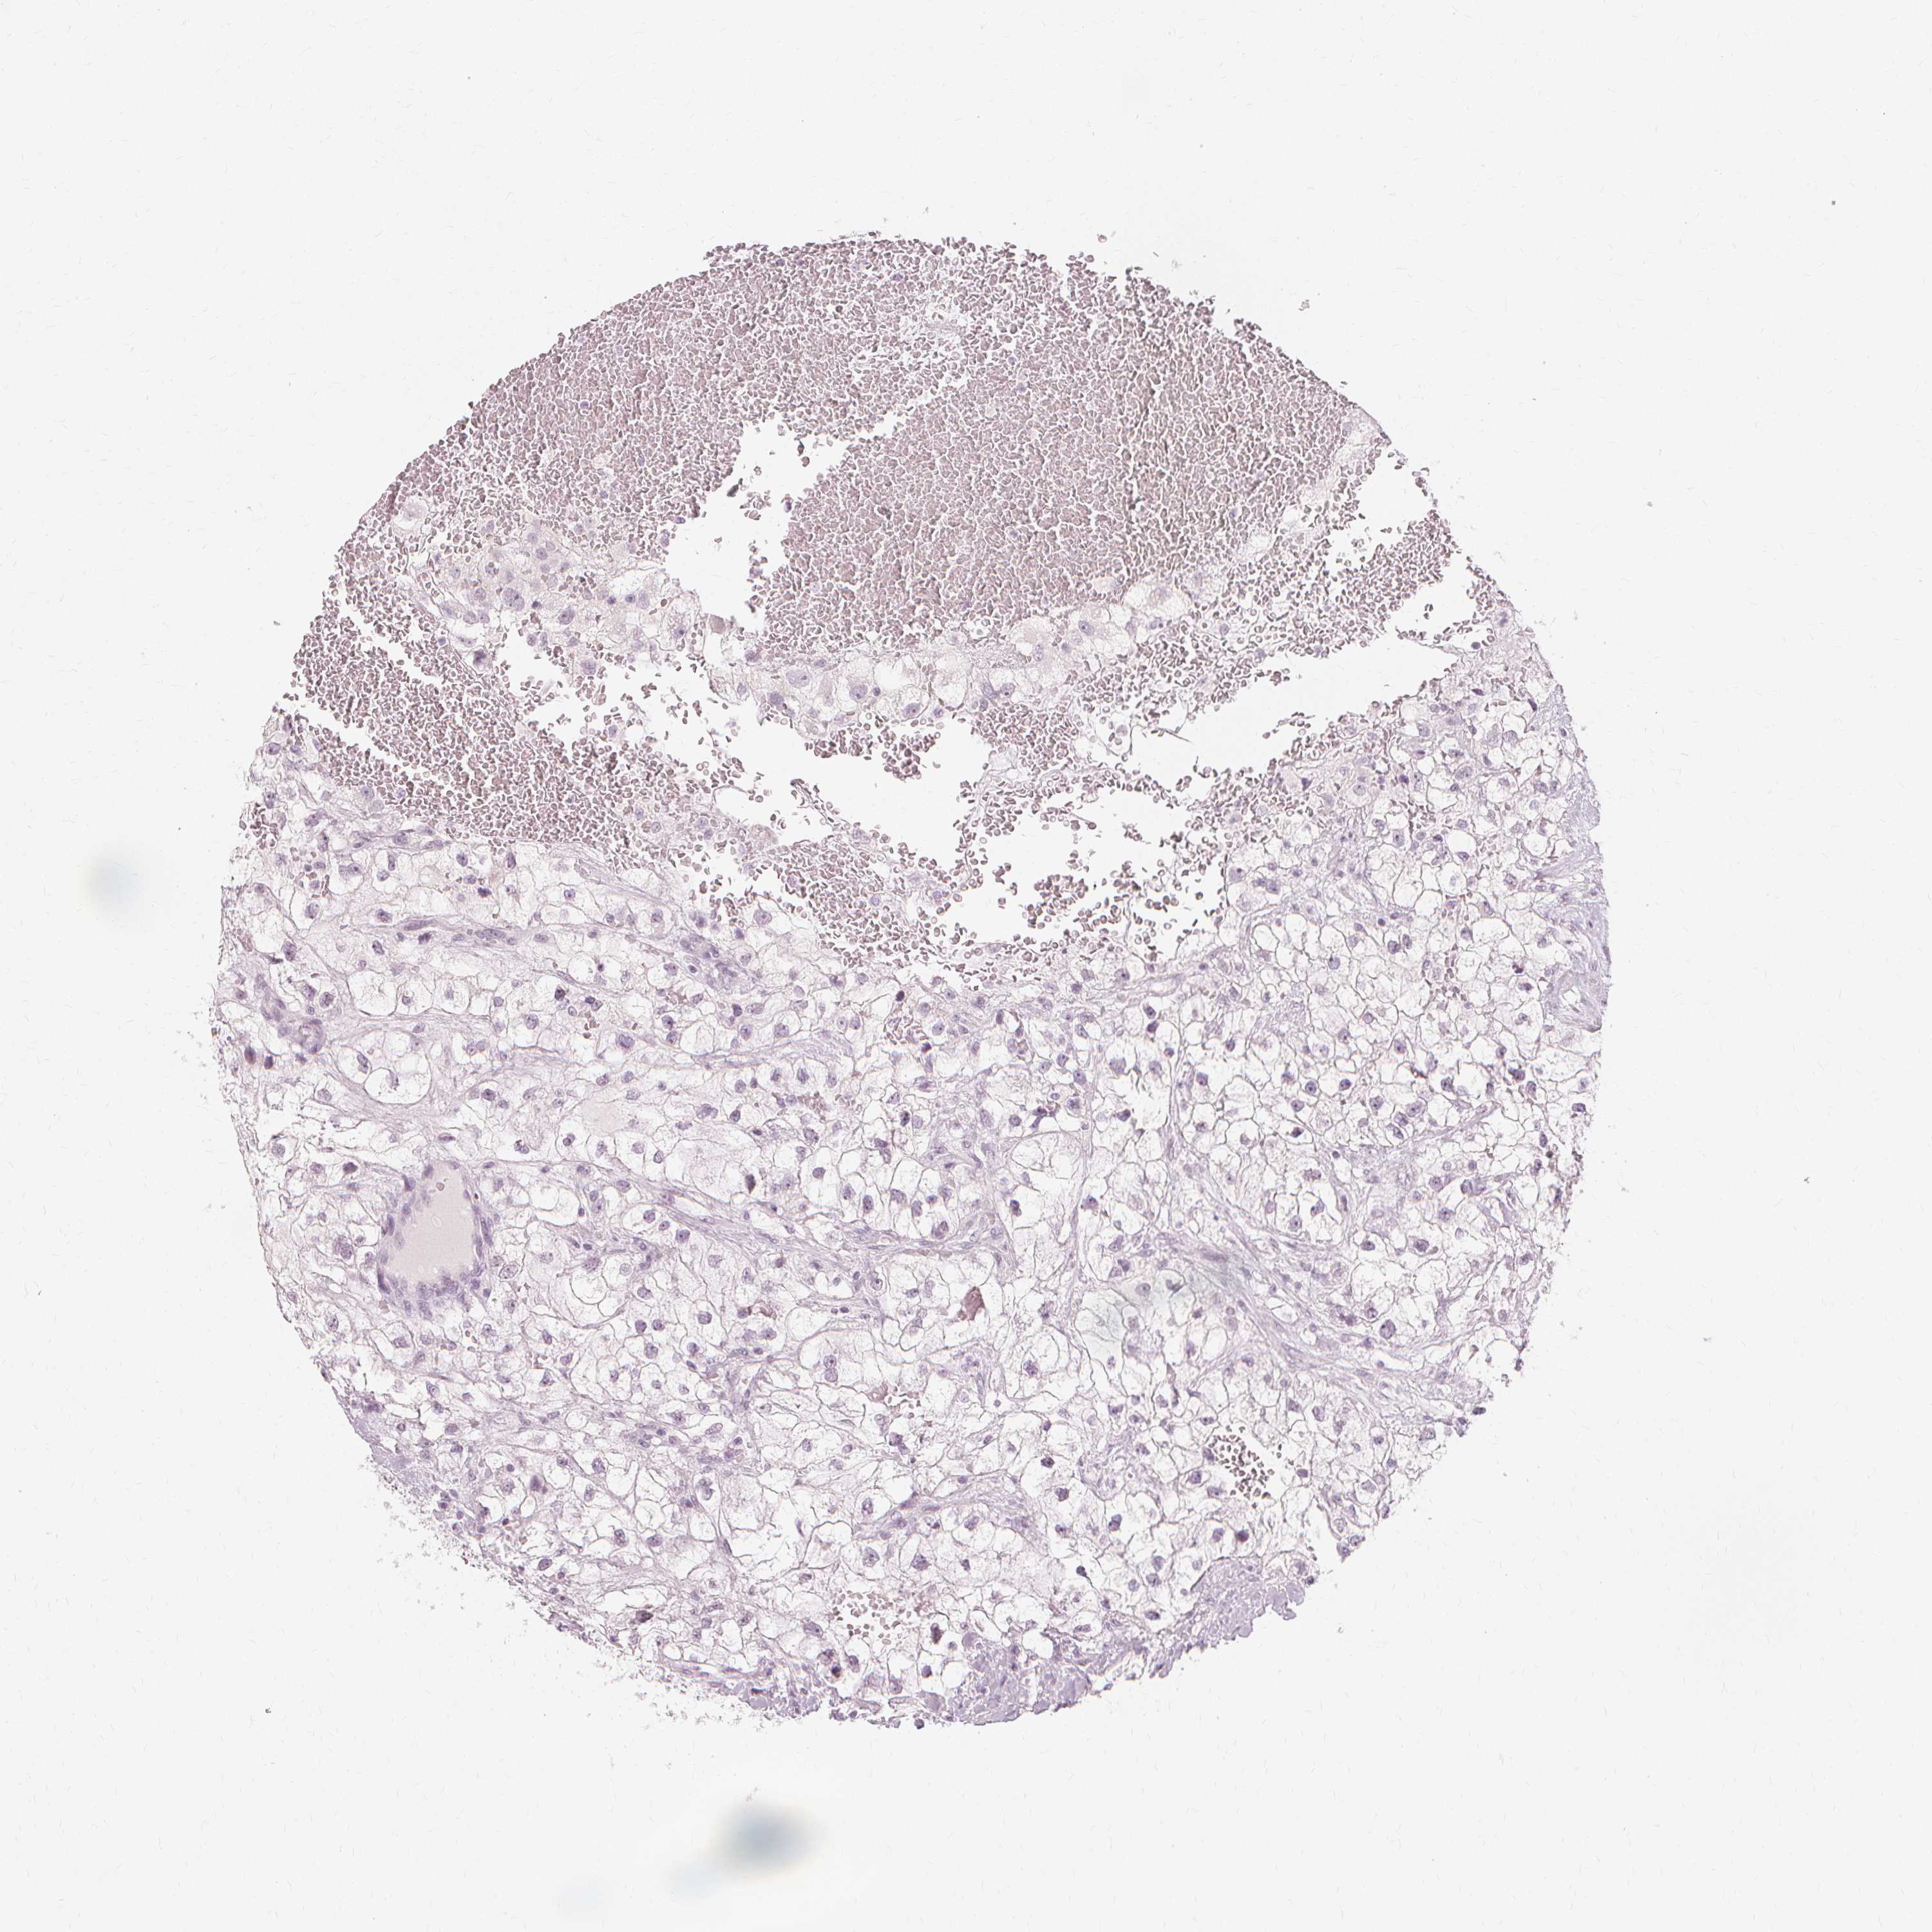

CANCER RENAL CANCER Show tissue menu

KICH TCGA KIRC TCGA KIRC VALIDATION KIRP TCGA PROTEIN RCC CPTAC PROTEIN EXPRESSION